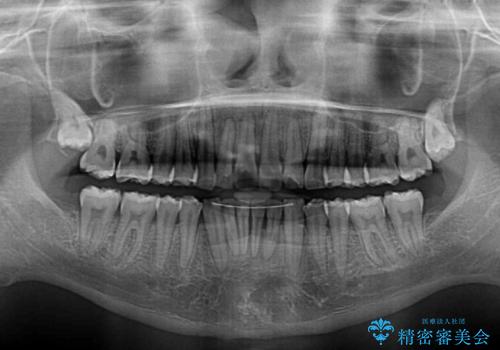

- 上下前歯のデコボコと、それに伴う出っ歯を気にして来院された患者様です。

インビザラインによる上下歯列の側方拡大と後方移動、IPR(歯と歯の間を削る)にるスペースの獲得により歯列を整えることとしました。

歯と歯の間を削ることでうまくスペースコントロールでき、また、毎日22時間以上しっかりとマウスピースを装着していただいたので、スムーズに治療が進みました。

治療途中で転勤となり、遠方からの通院となったため、来院間隔空いてしまいましたが、2年間で終えることができました。